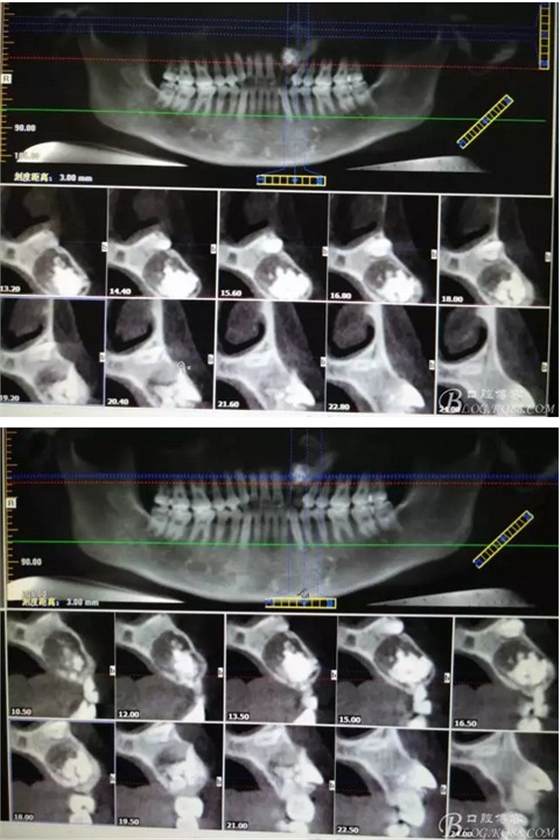

圖1。術(shù)前的CBCT影像檢查:22位于鼻底下方,23位于24、25的根方。左側(cè)乳Ⅱ、Ⅲ根方顯示囊性改變,囊腔內(nèi)大量致密鈣化團(tuán)塊,密度高。